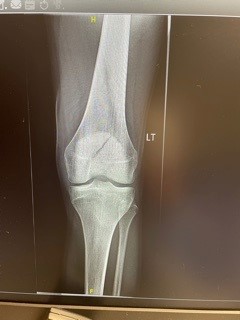

Once in the ER we had x-rays within minutes and soon found out Ty had fractured his patella which is commonly known as your kneecap. They said he must have banged it really hard to have broken it the way he did. Good God, I couldn’t believe it. We did get great treatment with Lori working there and everyone knowing it even though it was just Ty and I. I made sure to let everyone know who his mom was, ha. Meanwhile Lori was home with Dixie as she couldn’t leave her alone. We had a friend coming over but things were moving so fast I told her to just sit tight. I was taking photos of the x-rays and texting them to Lori who was texting them to Dr. Dorf from her office who then told us what to do. In the end Ty was put in an immobilizing brace and I took him home. It wasn’t easy getting him up and in the car as we have to keep his leg totally straight at all times but we managed. We made it home and got Ty upstairs. Monday morning we’ll follow up by going and seeing Dr. Dorf at Lori’s office. Looks like about 8 weeks on crutches but we think he’ll avoid surgery which is a big deal. Surgery could have meant months and months of recovery.

Obviously the knee on the right is the swollen one!

In the world of fractured knees, that’s one big break! Luckily he didn’t fracture his femur which is the bone above the break or it would have been surgery for sure. They tried to give Ty some pain medication when they showed up at the skate park as he was in tears when we moved him and I authorized it but then asked what they use and when they told me fentanyl I asked if they had anything less potent. They didn’t and Ty quickly spoke up and said he’d be fine. They asked him again at the hospital and he passed once again. I found out later one of his favorite musicians had over dosed on it and he wanted nothing to do with it. He’s a tough kid and has a high tolerance for pain but had to be in big time pain. All he had last night for pain was Tylenol even though they sent us home with Hydrocodone. He must have slept through the night as he’s still sleeping now. Poor guy, he has a concert in Salt Lake in two weeks that might be out now plus will be starting his senior year on crutches and was going elk hunting with me and James and his son at the first of September which now is out for sure. More to come in the next few days.